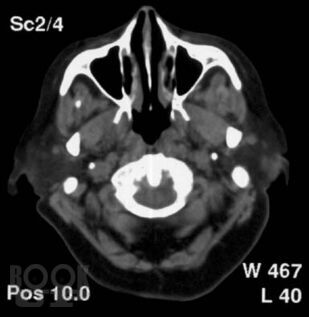

Монография основана на результатах исследований в отделении лучевой диагностики Института хирургии им. А.В. Вишневского РАМН. Представлена методика спиральной КТ шеи с внутривенным болюсным контрастным усилением. Изучена КТ-семиотика образований в нативную, артериальную, венозную и отсроченную фазы исследования. Представлены способы построения реконструкций (3D и MPR) патологических образований и структур шеи. Показаны возможности и эффективность нативной фазы КТ-исследования в диагностике липом и боковых кист шеи. Обоснована необходимость внутривенного усиления для выявления озлокачествления боковых и срединных кист. Значительная часть монографии посвящена дифференциальной диагностике объемных образований в области развилки сонных артерий: каротидных и вагальных хемодектом, неврином, исходящих из блуждающего нерва и симпатического ствола, а также аневризм сонных артерий. Показана возможность оценки взаимоотношения хемодектом с внутренней сонной артерией. Также оценена положительная сторона динамической КТ с внутривенным болюсным усилением в дифференциальной диагностике объемных образований шеи, и указаны ее недостатки в оценке взаимоотношения опухоли с сонными артериями на протяжении. При контрастном усилении выявлены дифференциальные КТ-признаки конгломерата лимфоузлов и первичных опухолей. Описаны некоторые редко встречающиеся опухоли и деформации шеи, симулирующие опухоли.